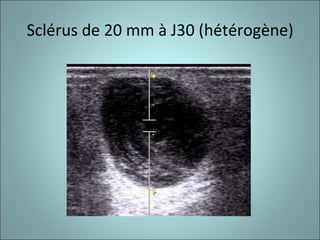

SCLERUS EN ECHOGRAPHIE (hétérogène).

Sclérus de 20 mm à J30 (hétérogène)

Sclérus de 20mm à J30 (hétérogène)